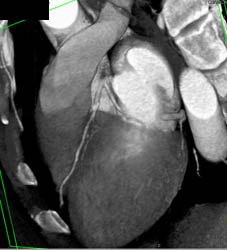

Plaque in LAD